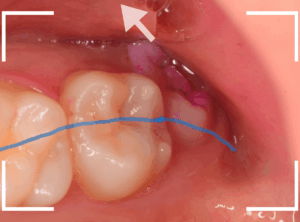

親しらずが頬や歯肉を噛んでしまう

上のケースのように歯並びの列から外れてしまったおやしらずに多いのですが、おやしらずが常に頬に触っている状態で、歯の頭(咬頭)が食事の際などに頬を擦ってしまい、裂傷になっています。

このような場合、患者さんは「歯が痛い」という訴えで来院される事が多いですが、見てみると頬や下顎の歯肉に傷があったりします。

当然、歯ブラシも満足に当てられませんし、抜歯一択ですね。